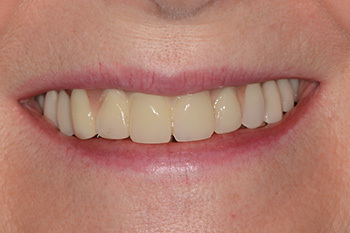

Le bridge provisoire (vue du sourire)

Vue externe du bridge d’usage au repos.